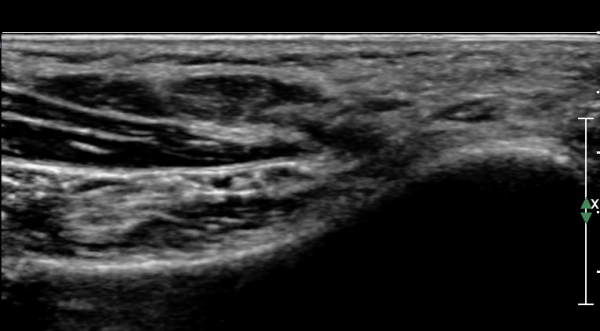

ÃÊÀ½ÆÄ°Ë»ç :  ¹ßµÚ²Þ ³»Ãø¿¡¼­ ¾Æ·¡µÚ²ÞÄ¡½Å°æ(inferior calcaneal nerve : Baxter's nerve) Ⱦ´Ü¸é °Ë»ç»ó

¹«Áö¿ÜÀü±Ù°ú Á·Àú¹æÇü±Ù(quadratus plantae) »çÀÌ¿¡¼­ ¾Æ·¡ µÚ²ÞÄ¡µ¿¸Æ ÈĹ濡 ¾Æ·¡µÚ²ÞÄ¡½Å°æÀÌ

Àú¿¡ÄÚ ¸ð¾çÀ¸·Î °üÂûµÈ´Ù(»çÁø 1, 2).